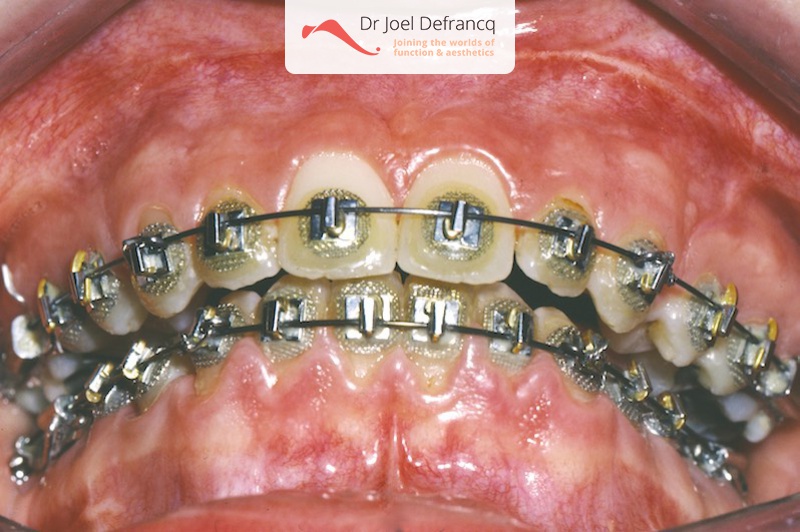

Darsa: Bovenkaak te groot en te veel naar voor

Diagnose van het gezicht

- Te grote bovenkaak

- Te kort gezicht